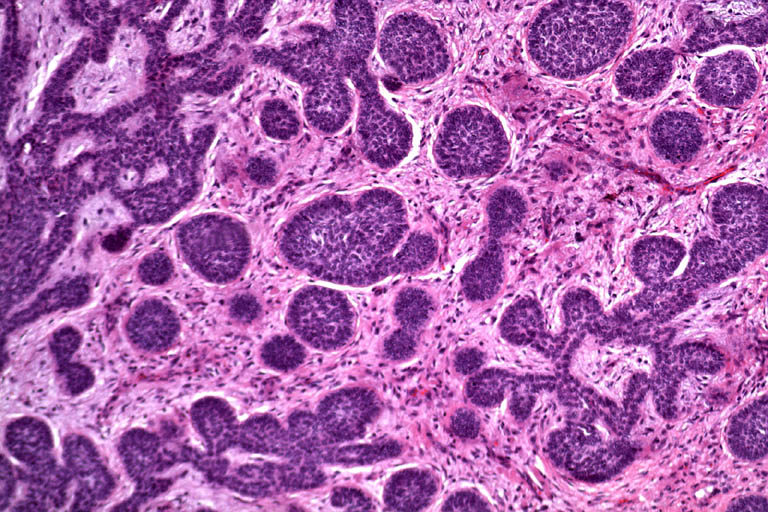

I ricercatori hanno infatti individuato la presenza del virus (famiglia polyoma) nei campioni di pelle di pazienti affetti da carcinoma squamoso, e il virus era anche stato capace di mutare per integrare il proprio Dna all’interno di quello delle cellule ospite. “Questa e’ una prova indiretta del del fatto che il virus ha un ruolo nello sviluppo di questo cancro”, ha detto Toland. “Il prossimo passo e’ scoprire come esso sia capace di integrarsi nel Dna delle cellule ospite.